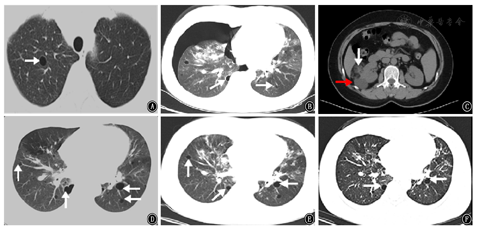

患者女,48岁,2001年在外院行纵隔淋巴结病理检查考虑诊断为"结节病",给予糖皮质激素类药物(泼尼松7.5 mg/d)治疗半年后自行停药,于2012年9月11日开始我院门诊复诊,胸部CT示:双肺门及纵隔淋巴结肿大,考虑结节病;首次发现右上肺气囊(图1A),此后多次复查胸部CT发现肺气囊稍有增加,未行诊治。之后于2016年11月5日患者无明显诱因出现自发性气胸至我院门诊行胸部CT示:右侧气胸,肺压缩约50%;双肺多发肺囊肿,双肺门淋巴结肿大(图2A),双肺弥漫分布为主(图1B),行胸腔闭式引流后复查胸部CT可见右侧气胸基本吸收。出院后又多次来我院门诊复诊查胸部CT仍可见双肺弥漫性肺气囊且数目逐渐增多,肺门淋巴结肿大较前略有缩小,遂调整为口服泼尼松(2.5 mg/d)维持,肺部气囊仍未行诊治。直至2019年5月11日至我院门诊复诊行泌尿系平扫CT又发现左肾乏脂肪错构瘤及右肾错构瘤(图1C),免疫病理:Melan-A(+),HMB-45(散在+),SMA(+),S-100(+),CD34(血管+),Desmin(局灶+),Ki-67(LI约10%+),H-Caldesmon(+),PCK[AE1/AE3](-)。综合考虑诊断为"右肾血管平滑肌瘤",给予抗感染、解痉及对症治疗,术后恢复可。术后规律复诊行胸部CT示:双侧肺气肿或肺气囊逐渐增多(图1D),考虑淋巴管平滑肌瘤病(lymphangiomyomatosis,LAM)可能,肺门淋巴结肿大较前明显缩小(图2B)。为求进一步明确诊断患者于2019年12月前往北京协和医院就诊,双肺CT示:双肺弥漫多发囊性病变,符合淋巴管平滑肌瘤;双肺门和纵隔淋巴结肿大,符合结节病表现;行68CA-NEB PET-CT符合肺淋巴管肌瘤病表现,行肺功能检查提示中度阻塞性通气功能障碍(FEV1/FVC 69.59%)弥散功能降低(DLCO SB 68.5%,DLCOCSB 68.5%),舒张试验阴性;ACE 21 U/L;VEGF-D 542 ng/L。综合考虑为"淋巴管平滑肌瘤病结节病",北京协和医院给予口服泼尼松2.5 mg(1次/d)、西罗莫司2 mg(1次/d)等治疗后稍好转,服用西罗莫司2个月后自行停用,继续口服泼尼松2.5 mg/d维持。于2020年5月6日患者因逐渐出现"气喘"和"呼吸困难"收入我院呼吸内科。查体:意识清楚、精神欠佳,双肺呼吸粗,双肺未闻及干湿性啰音。既往无吸烟,否认家族遗传病史。

入院诊断:淋巴管平滑肌病结节病。诊疗经过:入院后实验室检查:白细胞为4.99×109/L,中性粒细胞百分比79.2%,淋巴细胞百分比5.6%,可溶性抗原(ENA):抗核抗体(ANA-IgG)阳性,其他实验室检查结果均显示阴性。胸部三维成像CT仍可见双侧肺气囊,大小不一(图1E),双肺多发斑片影、双肺门淋巴结较以往增多、增大,考虑结节病进展?(图2C),支气管镜及病原学检测均未见异常。予以波尼松30 mg,1次/d口服治疗3周,每3周减少10 mg,直至维持量10 mg,1次/d,继续服用西罗莫司2 mg,1次/d治疗。治疗7天后复查肺功能:中度阻塞性通气功能障碍(FEV1/FVC为62%,FEV1%pred为82%,轻度弥散功能下降DLCO%pred为75%,DLCO/VA为91%)较之前外院复查肺功能稍有恶化。遗憾的是患者拒绝行肺气囊活检。2020年6月16日开始来我院门诊复诊,胸部CT示:双肺斑片状实变灶较前减少,肺部感染病灶较前大部分吸收(图1F)。肺门淋巴结肿大较前缩小(图2D),气喘症状改善。

LAM的影像学多表现为弥漫性分布的薄壁囊腔,多个肺叶的囊肿为特征,通常为双侧,一般无肺内结节影和间质纤维化特征,可伴发有气胸、胸腔积液及肺外血管平滑肌瘤等表现[5]。而结节病典型病理特征为非干酪性上皮细胞样肉芽肿,有可能仅表现出胸部影像异常,也可表现肺纤维化及呼吸衰竭的症状[6]。本文1例及国外报道的2例均符合上述影像学特征。有研究报道囊性肺疾病通常是发生在晚期纤维化的上肺门区域,可发生在结节病中,但这并不常见[7]。根据典型的影像学特征,首先推测本例的囊性肺病主要是由LAM引起。随后根据相关病理性特点,免疫组织化学染色显示平滑肌细胞阳性及特征性HMB45等均显示阳性,综合影像学表现及肺功能异常均是符合LAM病,但确诊仍还需要组织病理检查。激素联合免疫抑制剂治疗后复查肺功能及肺部气囊均无明显变化。考虑本例女性患者发病年龄较晚,LAM进展速度慢,继续随访观察。